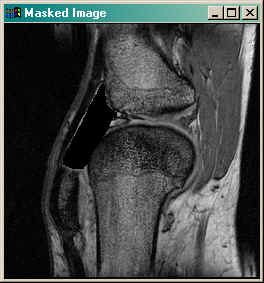

Now you are ready to use the image mask. Suppose, for example, that you want to turn all the pixels inside the ROI to 0 and leave the rest of the image intact. Then you would construct the mask and apply it to the image like this:

IDL> maskedImage = image * (1 - (mask GT 0)) IDL> TV, maskedImage

You see the result in the figure below.